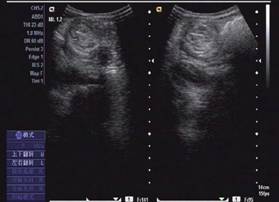

圖示:該患兒當時聲像圖表現(xiàn)

超聲圖像表現(xiàn)

1、腸套疊部位顯示邊界清楚的包塊。其橫斷面呈大環(huán)套小環(huán)的特征性表現(xiàn),即“同心圓征”或“靶環(huán)征”。外圓呈均勻的低回聲環(huán)帶,系鞘部腸壁回聲,低回聲帶系水腫增厚的反折壁及其與鞘部之間的少量腸內(nèi)液體形成。在大的外圓內(nèi),又有一個小低回聲環(huán)帶,形成內(nèi)圓。內(nèi)、外圓間為高回聲環(huán),中心部為高回聲團,其邊緣欠光整。套疊部的縱斷面呈“套筒征”或“假腎征”。有時可能顯示套疊的頂部和頸部,頂部呈指頭狀盲端。“假腎征”通常是在套疊時間較長,腸壁發(fā)生嚴重水腫時出現(xiàn),或是成人患者存在腸管腫瘤或息肉時出現(xiàn)。